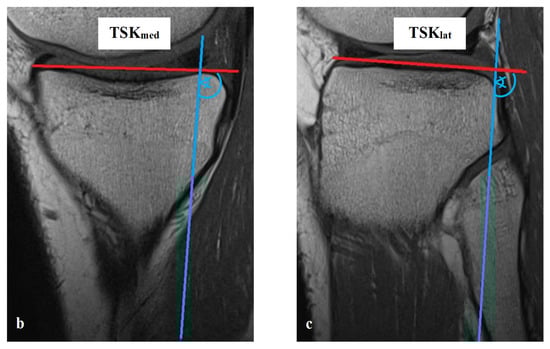

All measurements were taken via the PACS system (Picture Archiving and Communication System). Software from GE Healthcare called CentricityTM Universal Viewer was used (RA1000, edition 2019, Buckinghamshire, Great Britain). The osteoarthritis score of each knee joint was classified according to Kellgren/Lawrence (KL), in order to group patients as KJH or KJD. The TS was measured on the medial and lateral knee-joint surface according to Karimi et al. (TSKmed and TSKlat) [37] and Hudek et al. (TSHmed and TSHlat) [38]. As a reference for determining the inclination of the tibial plateau, Karimi et al. described the dorsal tibial bone cortex and Hudek et al. the tibial-shaft axis. Figure 1 and Figure 2 show the principle of the measurement methodology.

Figure 1.

Exemplary depiction of the measurements of the tibial slope according to Karimi et al. [37] for medial (TSKmed, (b)) and lateral (TSKlat, (c)) knee-joint surface: The measurements of TSK were performed in sagittal view of the knee joint in MRIs. To determine the right position of the dorsal tibial bone cortex for each TSKmed and TSKlat, a reference line was set in the best available image (a). Based on this reference line, the dorsal inclination angle of the tibial plateau was determined in the medial (TSKmed, (b)) and lateral (TSKlat, (c)) joint sections.